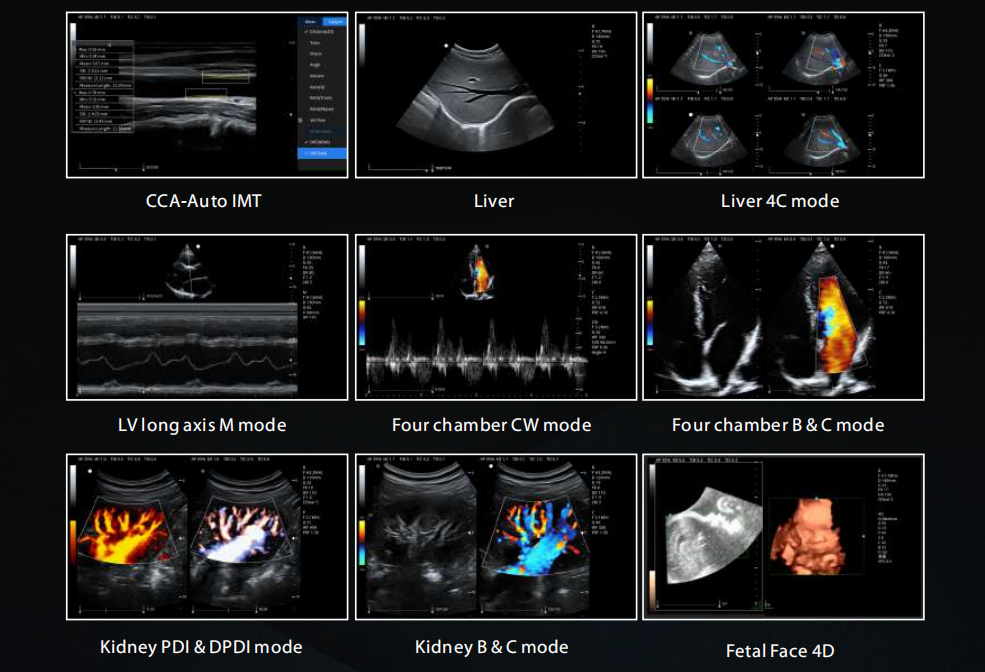

2D, CFM, M, PW, CW, CMM, DPDI, AMM, 3D/4D, ZPage, ZLive, TDI, elastography, panoramic imaging |

THI, SRI, SCI, TSI, FCI, EFOV, HR Flow, B Steering |

Standard automatic IMT measurement |

Supports local and global scaling |

Support PW automatic tracking and automatic calculation |